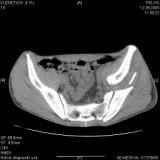

Уважаемые коллеги! Хотелось бы услышать совет по тактике лечения представлленого больного.Поступил после лечения в одном изотделений области. Травма 2,5 месяца назад. После выведенияиз шока был произведен остеосинтез перелома бедра, предплечья, до перевода к нам проводилосьвытяжение по оси шейки бедра за стержень, введенный в большой вертел. На сегодня деформацияригидна, клинически мобильности не определяется. Заранее признателен. P.S. Данный вид травм не включен в перечень "высокотехнологичных операций", направить длялечения по квотам Минздрава очень сложно.

Это обзорные и косые снимки

С уважением,

Привет, Леонид. Оскольчатый высокий двухколонный перелом в такие сроки трогать не надо, т.к. это про такие переломы сказано: "кто с ножом на Ж. пойдет тот в ней и останется...".